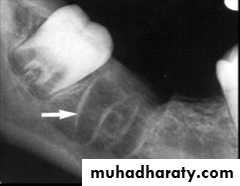

Radiographically is more radiodense due to presence of thick bone without trabeculations and is called as “lamina dura”

Alveolar bone proper has many openings for blood vessels and nerves – is perforated and is called as “cribriform plate”

Cribriform plate Vs Lamina dura